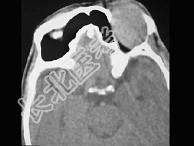

- 单项选择题男,45岁, 左眼疼痛伴视力下降一个多月,左眼明显外突, CT扫描如图所示,最可能的诊断是 ( )

A、左侧眶内炎性假瘤

B、左眶内血管瘤

C、左眶内纤维瘤

D、左眶内结核

E、左眶内转移瘤